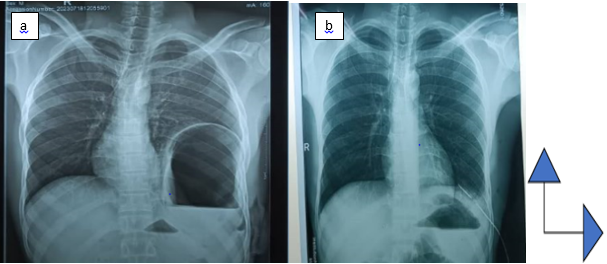

This was a 55-year-old patient, with no known pathological history, admitted to the emergency room for thoraco-abdominal trauma following a road accident. On clinical examination, the patient was conscious with good general condition. He was hemodynamically stable. Dyspnea was noted with a respiratory rate of 27 cycles/min, and oxygen saturation (SPO2) was 92% on room air. Dermabrasions were noted on the left hemithorax, asymmetry of the thorax and a decrease in the expansion of the left thorax. Auscultation found an abolition of vesicular murmurs in the left pulmonary field with a perception of hydro-aeric sounds. On abdominal examination, the abdomen was soft and painless. Hydro-aeric sounds perceived on abdominal auscultation. On additional examinations; an Emergency chest X-ray showed effacement of the left diaphragmatic dome, with passage of intra-abdominal viscera into the thorax strongly suggesting a diaphragmatic rupture. The left lung was pushed up and to the right (Figure 1). The thoraco-abdominal CT scan was requested but not performed. The biological assessment (hemogram, azotemia and creatinine) was normal. The patient was blood group O rhesus positive. We considered the diagnosis of a traumatic rupture of the diaphragm with repercussions on the ventilatory function and we indicated surgical management. Under general anesthesia, the approach was made via the left subcostal abdominal route. Exploration revealed the presence of the stomach and spleen ascended into the left hemithorax through a 4 cm diaphragmatic breach (Figure 2). The placement of a gastric tube allowed the stomach to be emptied and respiratory function to be improved. A lowering of the stomach and spleen ascended intra-abdominally is performed. The placement of chest drains preceded the diaphragmatic suturing by interrupted stitches with non-absorbable thread and the placement of a chest drain opposite the suture. The postoperative course was simple with the removal of the drain on day 5. The patient was discharged from the hospital on day 7 postoperatively in good health. Over a 6-month follow-up, no complaints were reported by the patient who had resumed his daily activities.

Figure 1 Emergency chest X-ray showing a left intrathoracic hydroaeric image with the ascension of the diaphragmatic dome (a). Postoperatively, the disappearance of the hydroaeric image without re-amplification of the left hemi-lung (b).